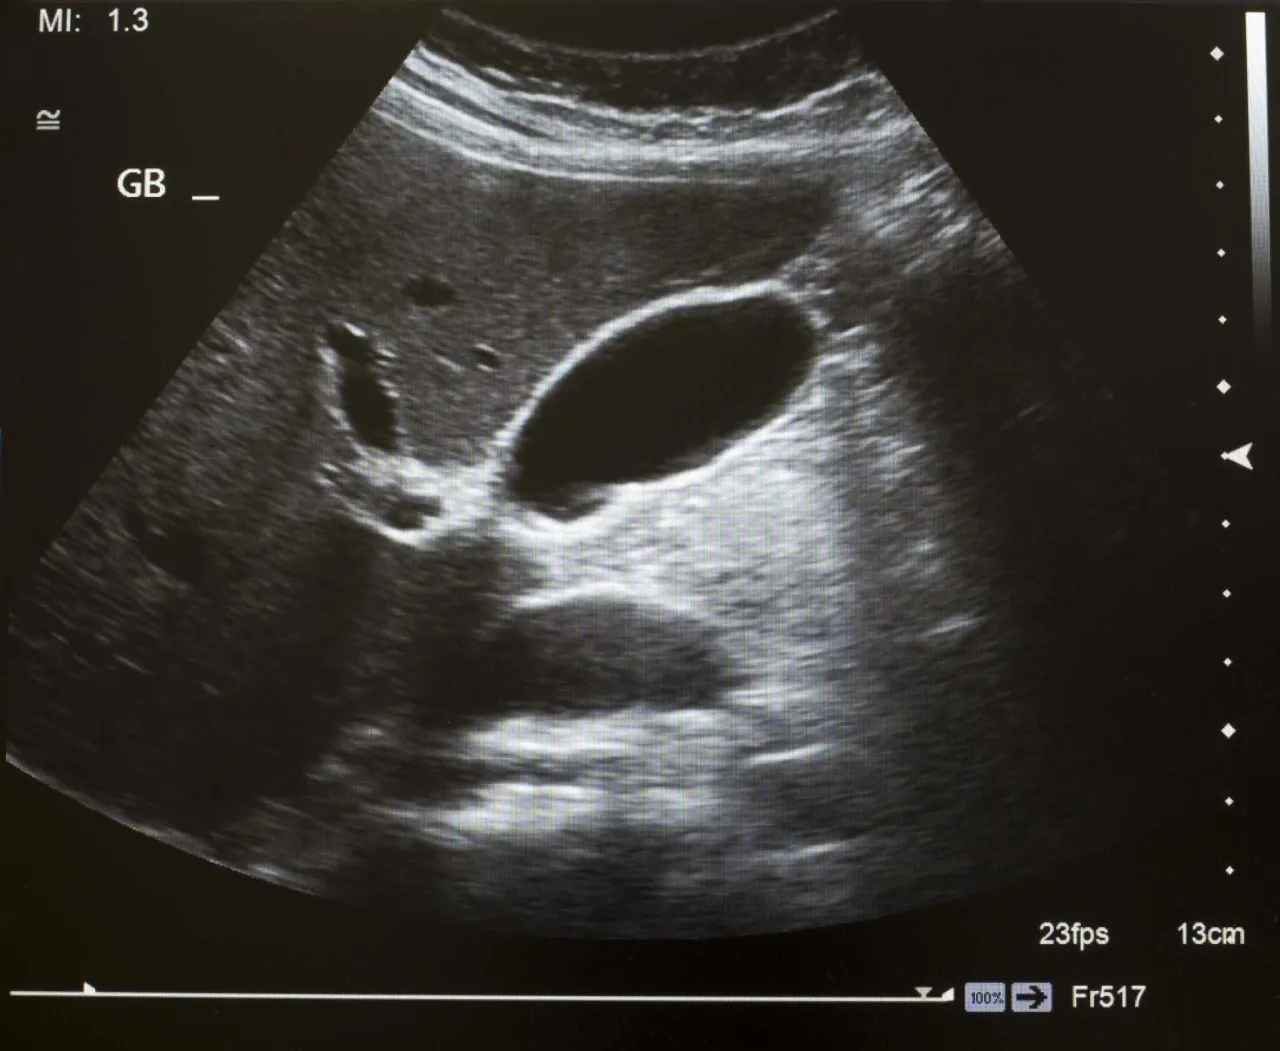

- Ultraschalluntersuchung (Sonographie): Dies ist die Methode der Wahl zur Diagnose von Gallensteinen. Die Ultraschalluntersuchung des Bauches ist schmerzfrei, benötigt keine Vorbereitung (außer Nüchternheit) und ist für den Patienten strahlenfrei. Sie liefert sehr zuverlässige Bilder der Gallenblase und der Gallengänge und kann Gallensteine, aber auch Entzündungen oder eine erweiterte Gallenblase gut darstellen.